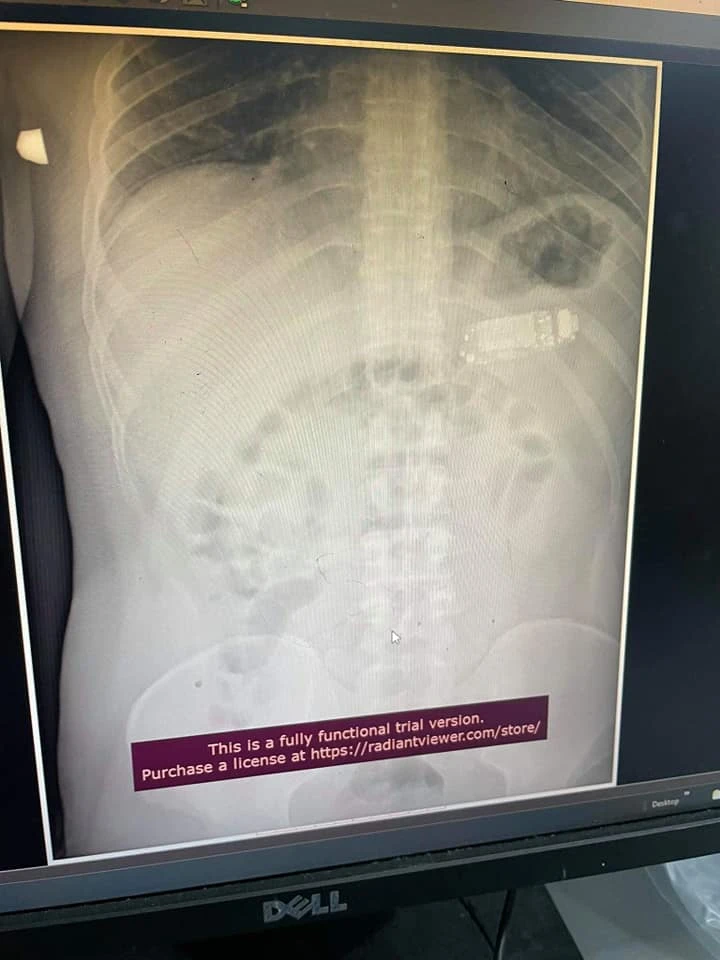

Kosova'nın başkenti Priştine'de doktorların önüne oldukça ilginç bir vaka geldi. 4 gündür midesinde cep telefonuyla gezen kadın, geçtiğimiz gün ameliyata alındı.

Ameliyatı yapan ekibin başındaki doktor Skender Teljaku, kimliği açıklanmayan 33 yaşındaki hastanın karnından çıkarılan Nokia 3310'u telefonunun fotoğrafını sosyal medya platformu Facebook'da paylaştı.

Doktor, paylaşımında endoskopi görüntülerine de yer verdi. Teljaku ameliyatın öncesinde hastanın karnını açmadan özel bir endoskop cihazıyla telefonu üç parça haline böldüklerini söyledi. Newsweek'in haberine göre, telefonun en tehlikeli parçasının bataryası olduğunu belirten doktor, bataryanın patlaması durumunda kimyasalların organlara bulaştırabileceğini belirtti.